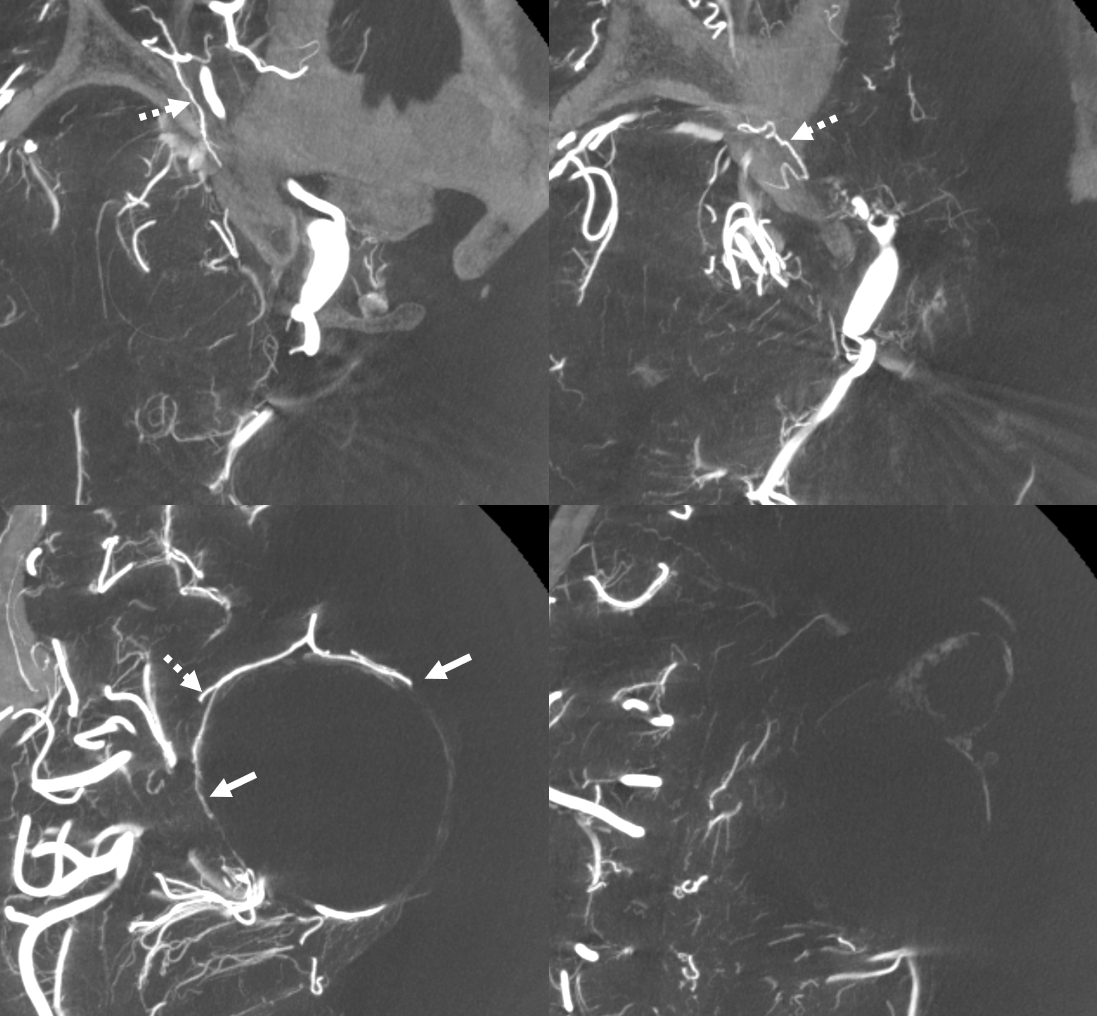

Video — Siemens Q, FOV 22 micro, 10 sec DCT, 3 cc/sec for 36 ccs 2 sec delay. Thin axial MIP

A better image is obtained a bit later on Siemens Icono 7 Sec dual volume DSA DCT unbinned micro FOV = 22 cm, injection 3 cc/sec for 30 ccs 3 sec delay 100% contrast

Stereo Pair volume rendered images

with arrows